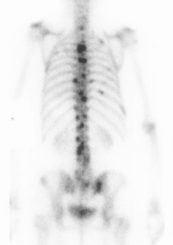

Bone Scan

1. Identify margins for resection / identify skip lesions

2. Identify metastatic disease

Bone scan with isolated disease

Bone scan metastasis